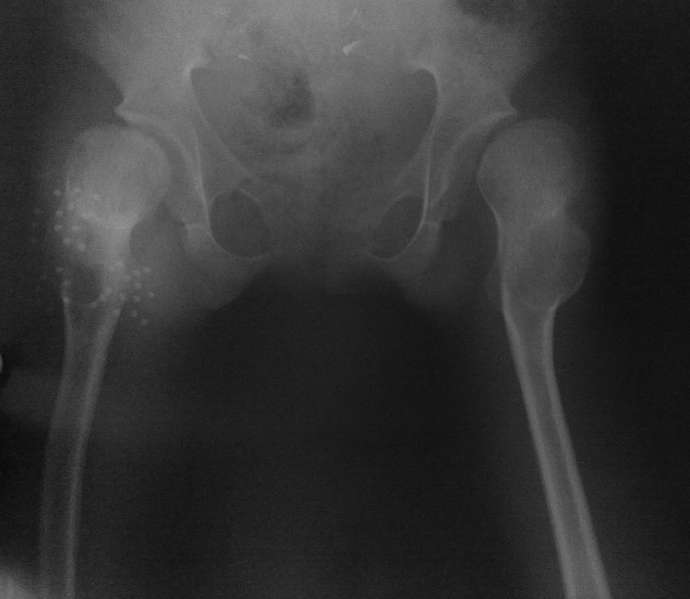

Ребенку 14 лет. 3 недели назад дома упала. На рентгенограмме диагностирован вывих в правом тазобедренном суставе.

Под общим наркозом вправлен. 2 недели ребенок находился на лейкопластырном вытяжении. В связи с тяжким состоянием ребенка (диспептические явления, задержка стула, носовые кровотечения, начальные явления застойной пневмонии) вытяжение снято. сразу после чего сделано рентген контроль (фото 1). а через неделю, то есть сегодня сделан второй снимок (фото 2). Где видно повторный вывих.

На рентгенограмме видно, что в 3 месячном возрасте не была диагностирована тяжелая форма дисплазии с подвывихами, где, кроме вывиха, имеет место непролеченные диспластические суставы с обеих сторон, больше справа.

Ни скелетное, ни лейкопластырное вытяжение за бедро долго не выдержит. Даже если вправить вывих, он повторится в силу диспластичности сустава.